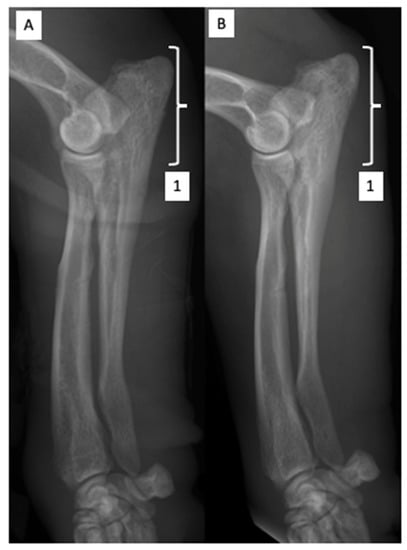

2.2. Orthopedic Examination and Radiological Findings